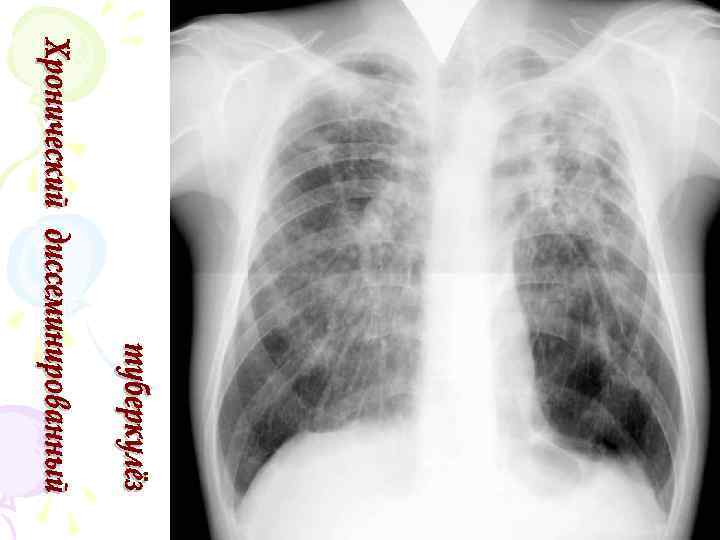

Рентгенологическая картина • Наблюдается полиморфная картина: очаги различной величины, формы и интенситвности, свежие и старые на фоне фиброзных изменений, больше в верхних отделах • Тенденции к слиянию очагов нет • Нарушается симметричность поражения • Могут наблюдаться как тонко- так и толстостенные каверны • Верхушки - интерстициальный фиброз, уменьшение объема, плевральные наложения, в нижних отделах - викарная эмфизема. С-м плакучей ивы. • Тень сердца сужена, имеет срединное положение (капельное сердце) • Фиброз и эмфизема обуславливают деформацию бронхиального дерева, что способствует развитию бронхоэктазов